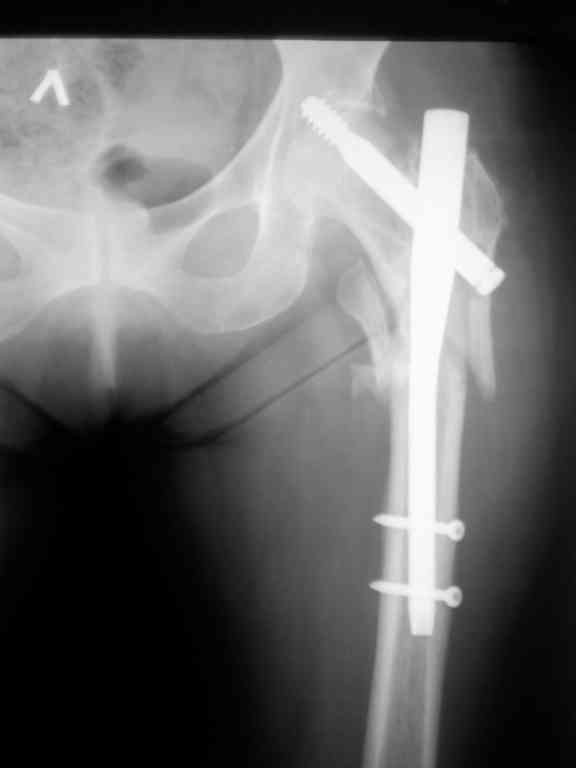

Перелом тут больше подвертельный. Нагрузка без торцевого упора на уровне перелома привела к телескопированию отломков на стержне. Ну и варус небольшой тоже свою лепту внес - если бы его не было, контактирующие латеральные стенки обоих отломков предотвратили бы укорочение, да и срослось бы за пару месяцев. А раз не срослось, упора отломков нет, более слабым местом оказались не нижние винты, а кость в головке и шейке. Так что надо было хотя бы удалить нижние винты до начала полной нагрузки.

На мой взгляд, причиной телескопирования явилось несоответствие диаметра гамма нэйл с диаметром канала подвертельного отдела бедра: обратите внимание на величину протрузии шеечного винта и величину медиализации дистального фрагмента - они одинаковы, смещение или телескопирование фрагментов происходило до того момента, пока гамма нэйл не упёрся в медиальный кортекс и образовалось пространство между латеральным

кортексом и латеральной поверхностью гвоздя.

В приложении похожий пример, к счастью, пациентка появилась не после, а "за полчаса" до протрузии. Пересинтезировали с исправлением ошибок.